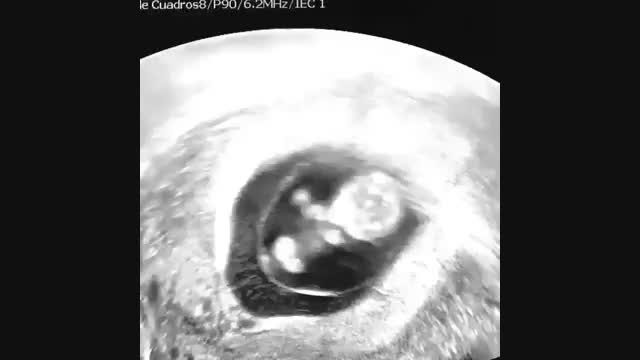

حرکت جنین

مرکز تصویربرداری پزشکی نماطب در شرق تهران در زمینه سونوگرافی، سی تی اسکن و MRI بهترین خدمات را ارائه می دهد. جهت ارتباط با این مرکز با شماره های 77508771-77501297 تماس حاصل فرمایید.